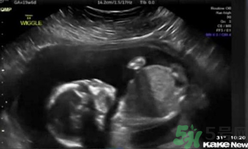

還只有5個(gè)月半的胎兒居然自己打自己的臉,這也太奇葩了,將來可能是個(gè)拳王啊。~美國堪薩斯州一個(gè)5個(gè)月半大的胎兒在母親子宮內(nèi)打自己的臉并把自己擊倒,這一幕剛好被父母用超聲波檢測(cè)儀記錄了下來,并被分享到網(wǎng)上,引得眾人稱奇。這對(duì)夫婦原本還擔(dān)心兒子可能會(huì)有腦震蕩,但護(hù)士讓他們放心。凡妮莎說,這次的事件導(dǎo)致他們開始考慮兒子的個(gè)性:“我們倆都愛終極格斗。所以我們正在討論他或許會(huì)成為一個(gè)拳擊手?!?/p>